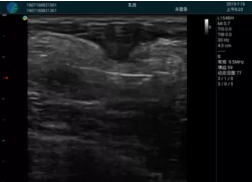

M20實時引導(dǎo):向包塊后方間隙注射利多卡因

清晰顯示腺體內(nèi)低回聲快影,邊界清晰,包膜較光滑